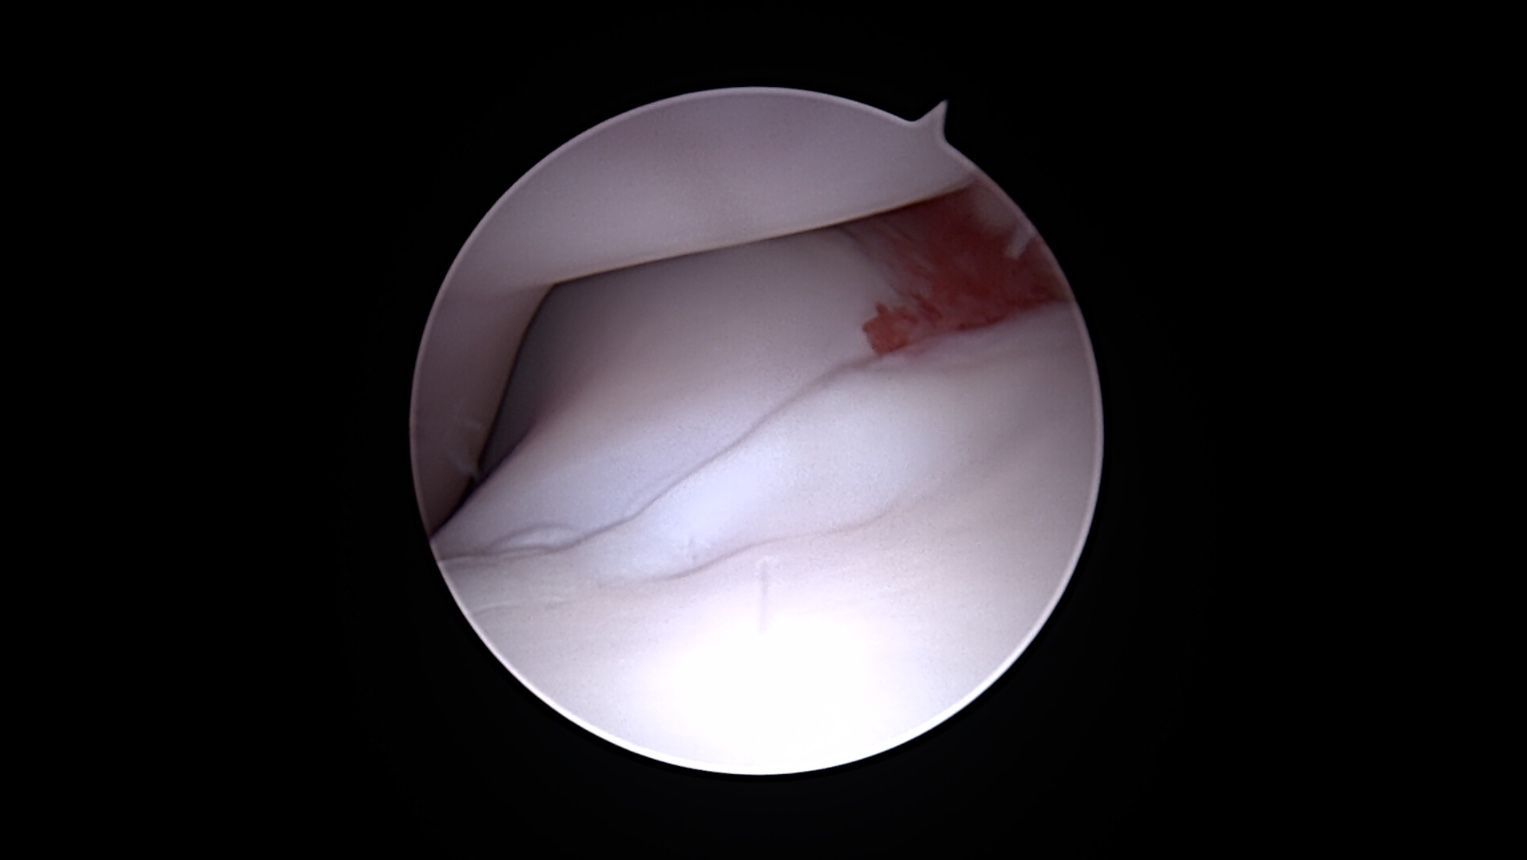

Lésion débutante coronoidienne

Arthroscopie du coude montrant une fragmentation du processus coronoide médial